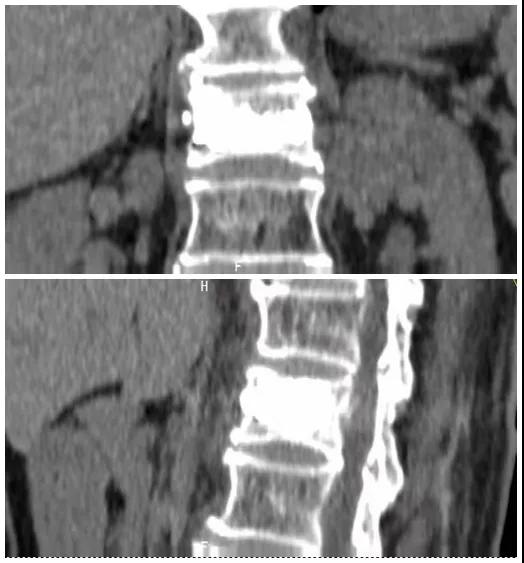

術后復查CT可見骨水泥彌散充分